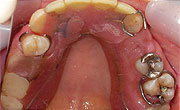

入れ歯(義歯)は一患者さんひとりひとりそれぞれ違い千差万別です。入れ歯をつくった当初は問題がなくても経年的変化により、だんだんとお口に合わなくなってくることがあり、調整が必要となってきます。

合わない入れ歯を我慢して使用すると、ますます噛めないばかりではなく、口の中の環境が悪くなってしまいます。入れ歯のことでお悩みの方は、ぜひご相談下さい。